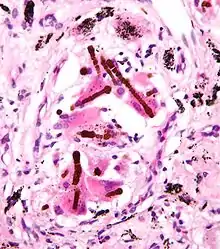

Ferruginous bodies. H&E stain.

They appear as small brown nodules in the septum of the alveolus. Ferruginous bodies are typically indicative of asbestos inhalation (when the presence of asbestos is verified they are called "asbestos bodies"). In this case they are fibers of asbestos coated with an iron-rich material derived from proteins such as ferritin and hemosiderin.[1] Ferruginous bodies are believed to be formed by macrophages that have phagocytosed and attempted to digest the fibers.